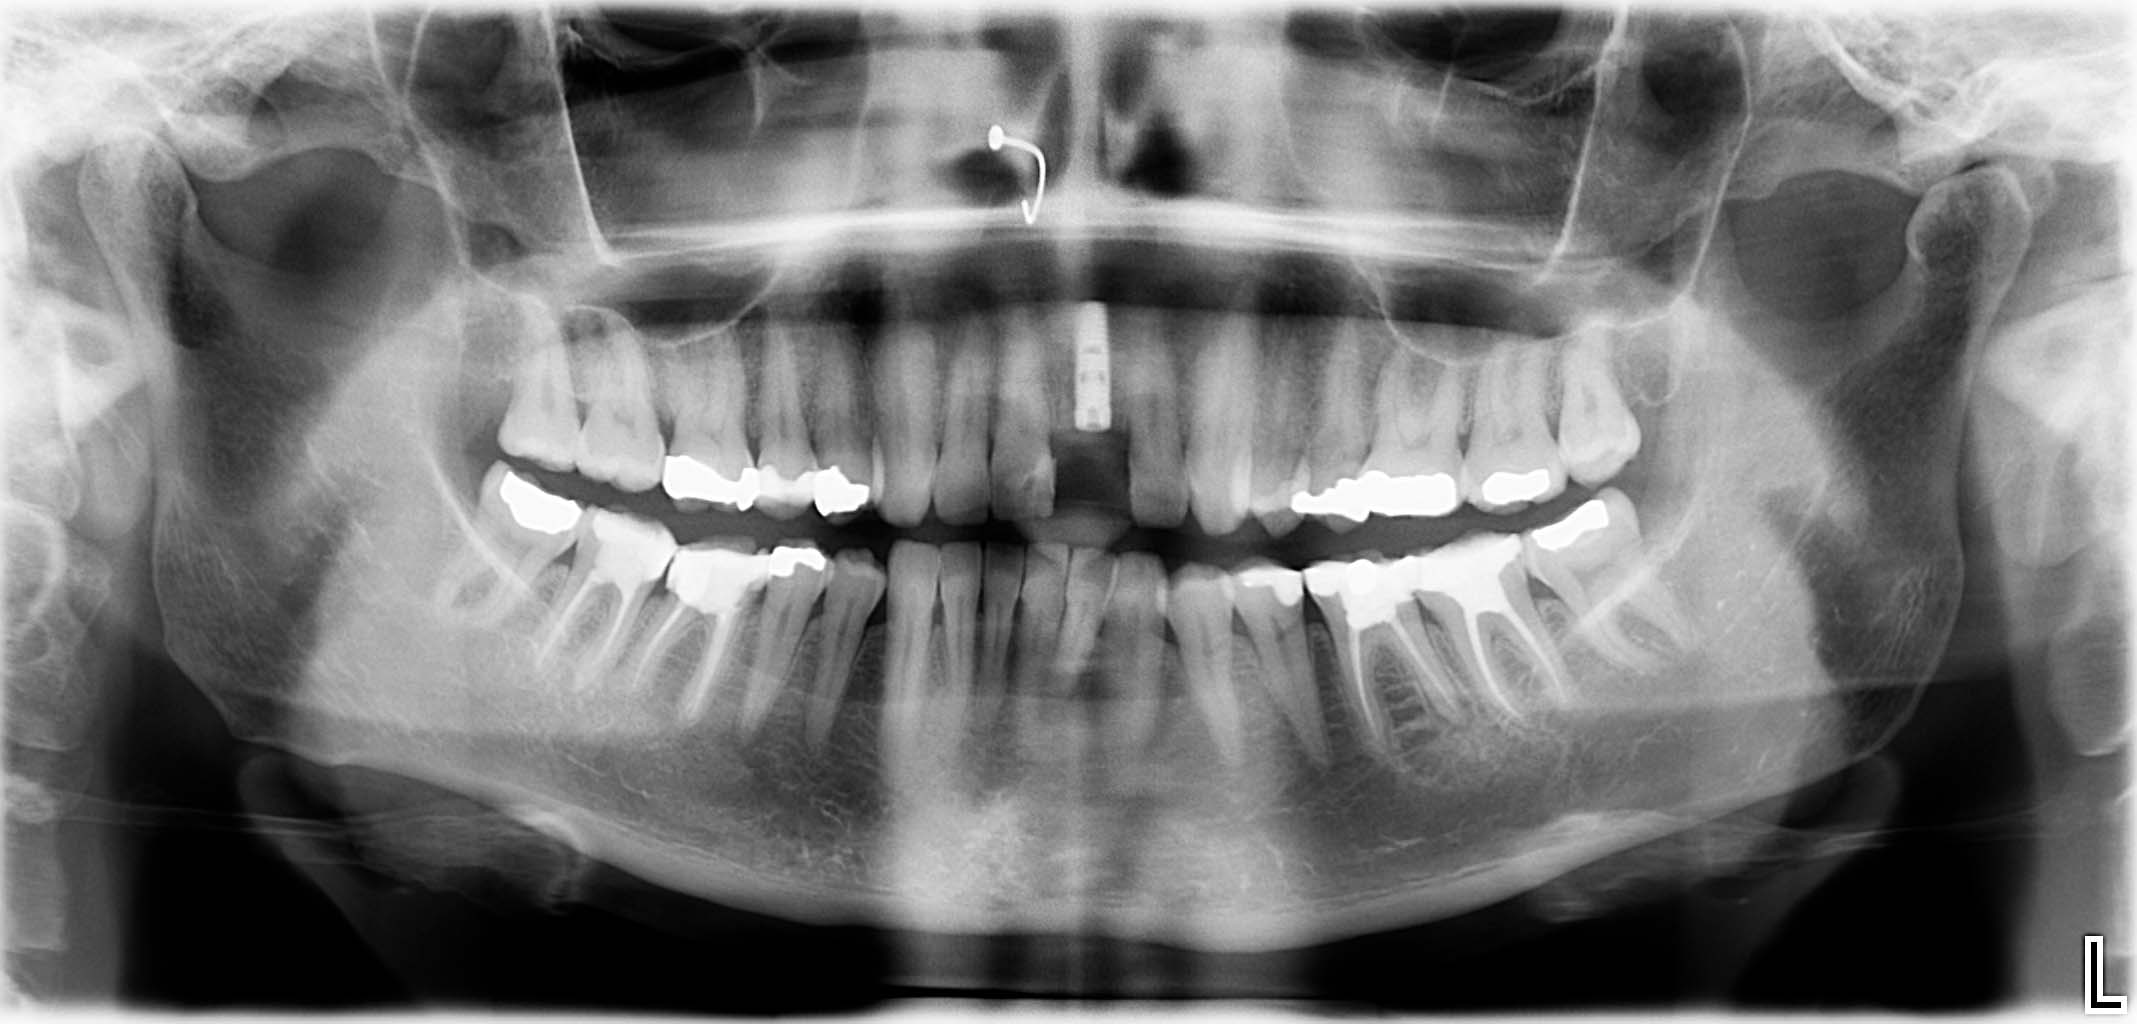

Erfolgreich implantierte Patientenfälle (klinische Fotos)